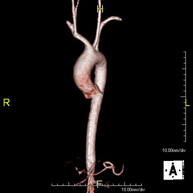

Prueba diagnóstica no invasiva que consiste en el estudio de la arteria aorta abdominal, obteniendo imágenes de alta definición anatómica mediante el empleo de un campo electromagnético y ondas de radio (con un emisor y un receptor). Es indispensable el uso de contraste paramagnético (Gadolinio). Sin embargo, no utiliza radiación ionizante. La calidad de las imágenes permite realizar reconstrucciones en 2D y 3D. Está indicado en aquellos pacientes con enfermedad vascular (aterosclerosis), estudio de aneurismas, en estudios pre-quirúrgicos de lesiones adyacentes a la aorta abdominal como "mapa" vascular, etc. - Angio RM Aorta-ilíaca

Prueba diagnóstica no invasiva que consiste en el estudio de la arteria aorta abdominal de las arterias ilíacas, obteniendo imágenes de alta definición anatómica mediante el empleo de un campo electromagnético y ondas de radio (con un emisor y un receptor). Es indispensable el uso de contraste paramagnético (Gadolinio). Sin embargo, no utiliza radiación ionizante. La calidad de las imágenes permite realizar reconstrucciones en 2D y 3D. Esta prueba está especialmente indicada como estudio pre-quirúrgico (mapa vascular) antes de intervenciones percutáneas o quirúrgicas de aorta abdominal y arterias ilíacas, estudio complementario en pacientes con isquemia de miembros inferiores, etc. - Angio RM Arterial extremidades inferiores